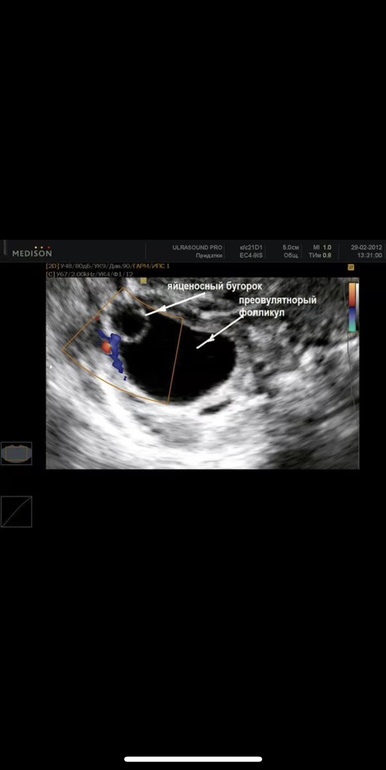

Я не специалист узи, просто когда мне сказали, что фолликул вырос на 28мм, я стала в интернете смотреть как выглядит лопающийся фолликул и на сколько страшно, что он 28 мм. И была картинка с бугорком, и с моментом выхода яйцеклетки на узи. Очень похожа на вашу.

Это с яйценосным бугорком Ваш тоже чем-то похож, только будто ваш бугорок уже лопнул.